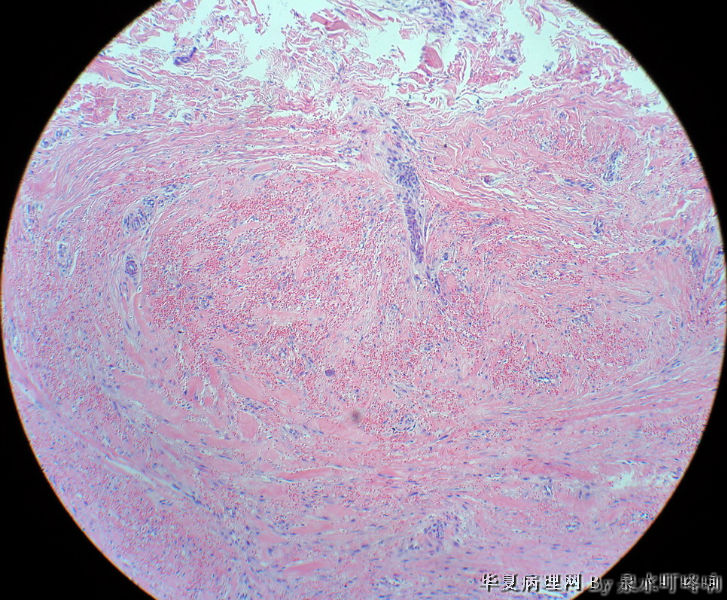

男,49岁,左肩胛部肿物。

图1